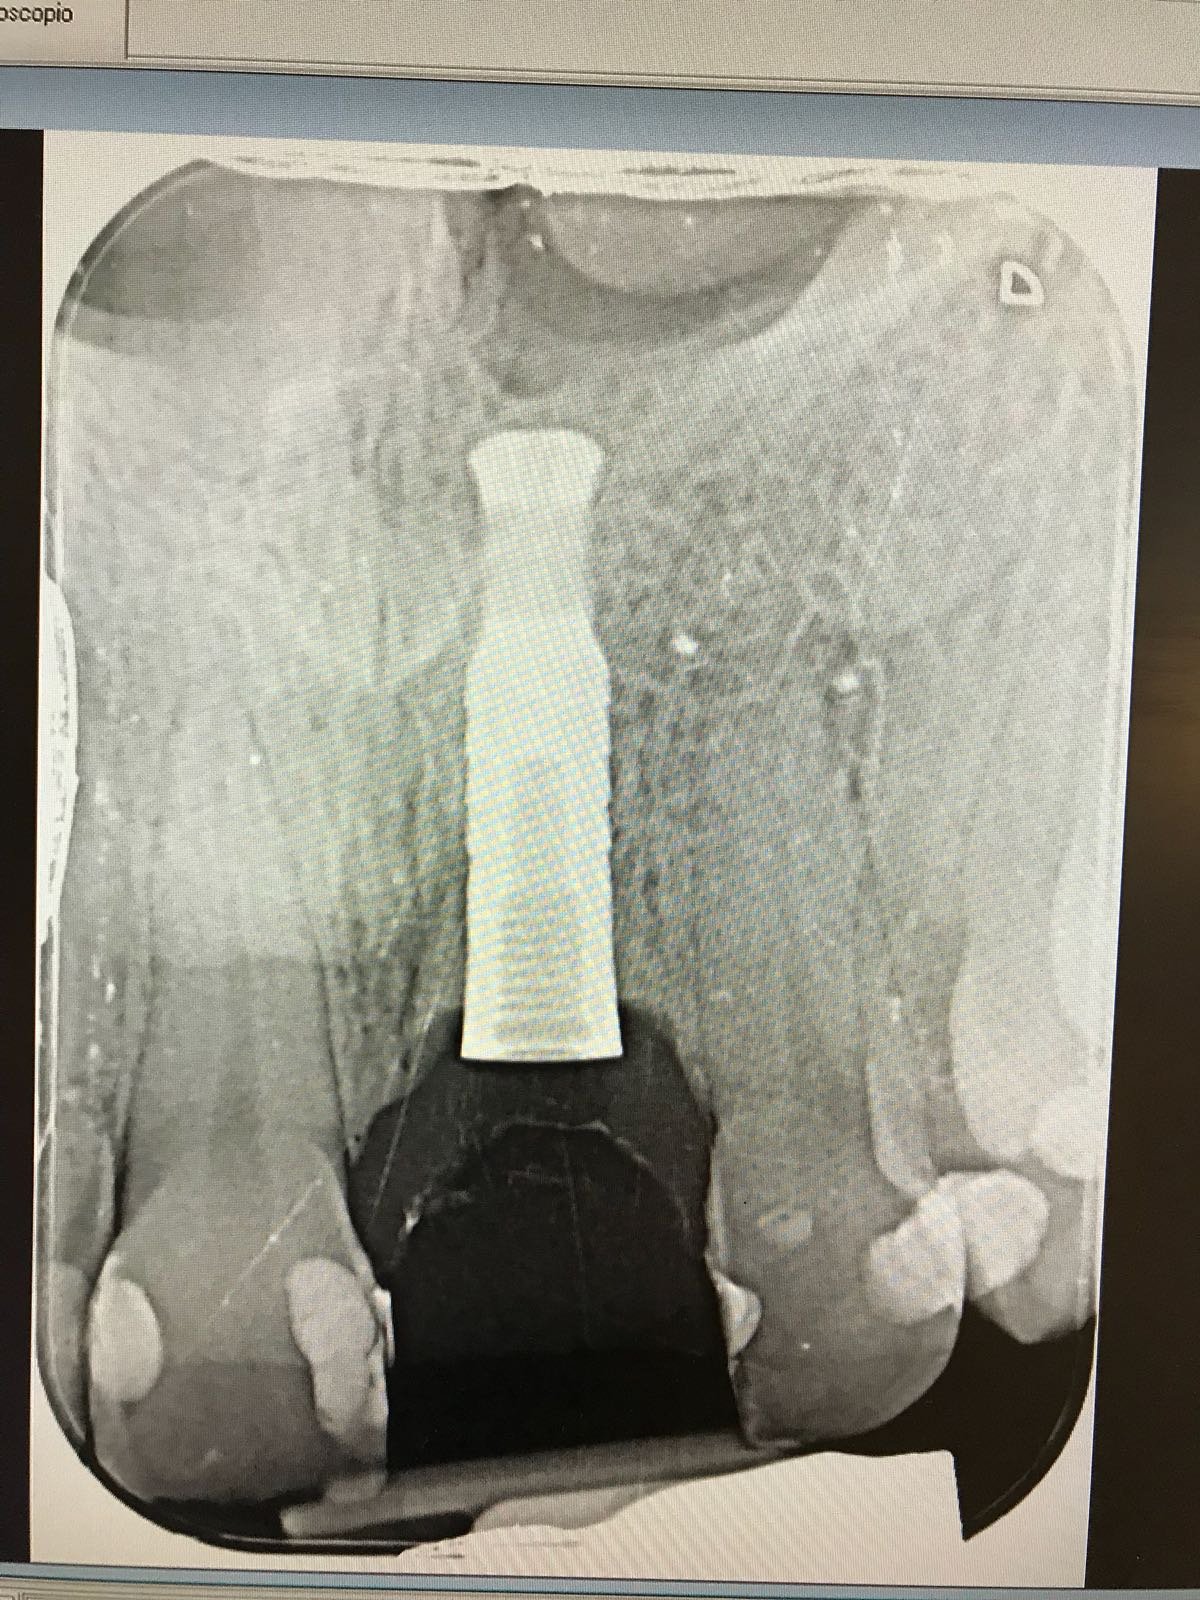

No se que implante y conexiones compatibles puedo utilizar para reponer la corona.

Se trata de un implante de conexión interna colocado hace mas de 20 años nos comenta el paciente.